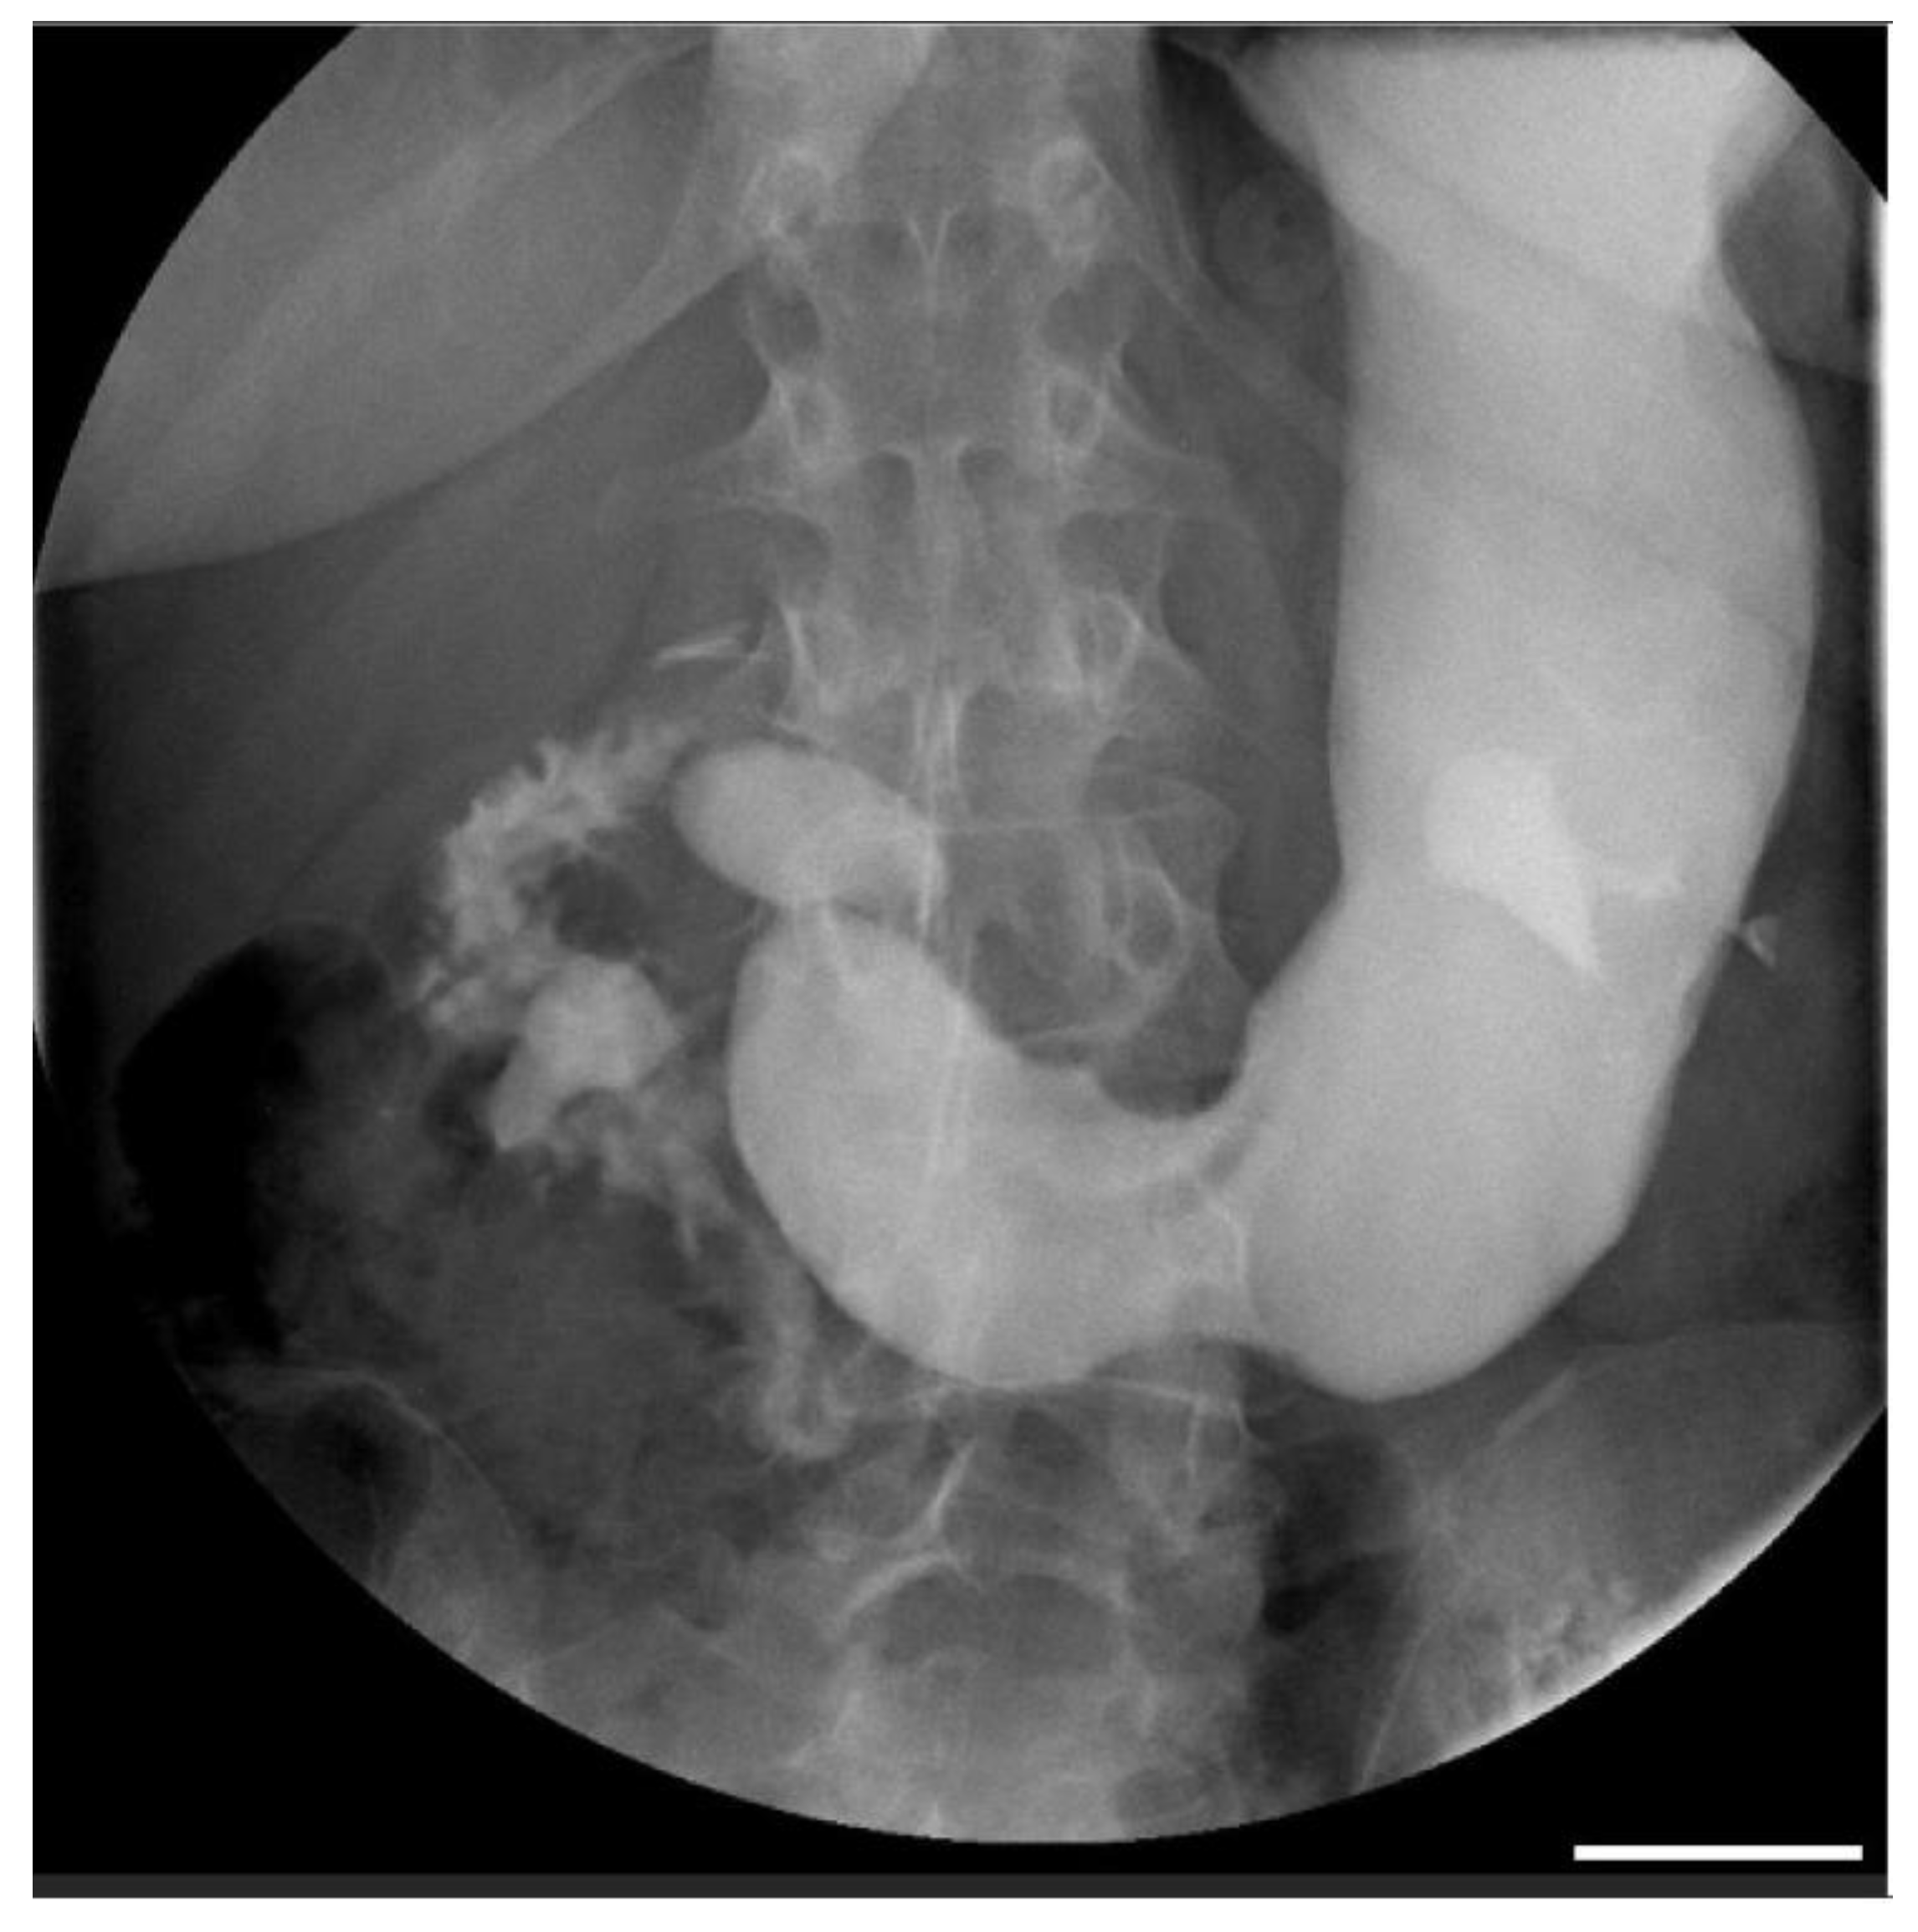

2. Case Report